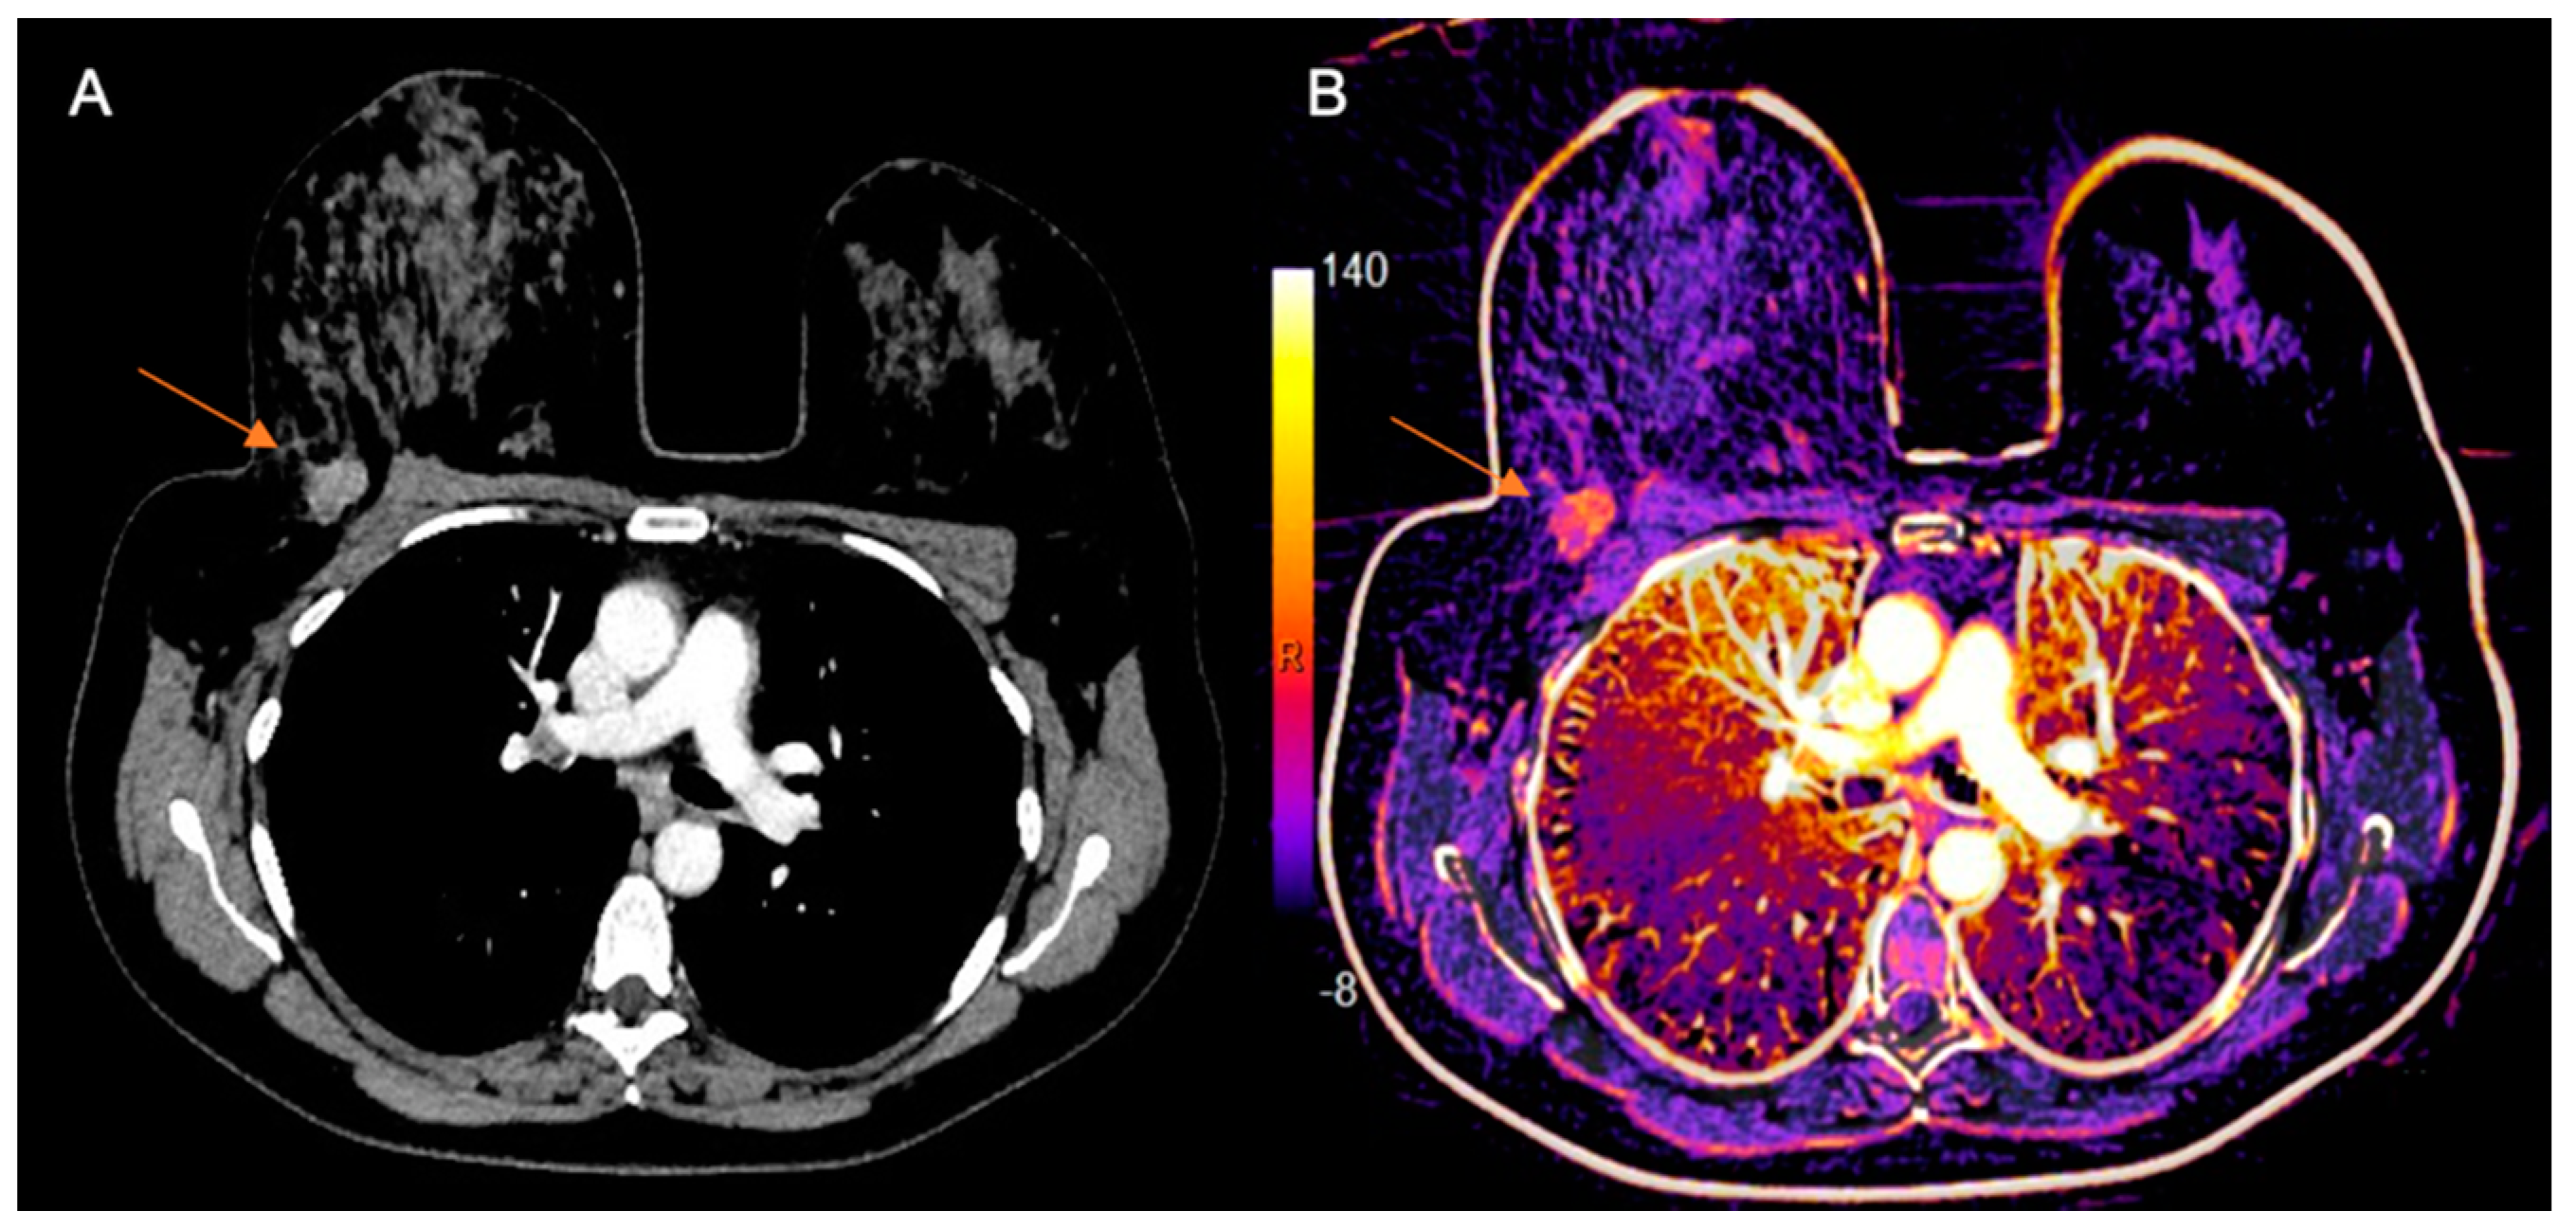

- Volterrani, L.; Gentili, F.; Fausto, A.; Pelini, V.; Sardanelli, F.; Mazzei, M.A.; Volterrani, L.; Gentili, F.; Fausto, A. Dual-Energy CT for Locoregional Staging of Breast Cancer: Preliminary Results. Am. J. Roentgenol. 2020, 214, 707–714. [Google Scholar] [CrossRef] [PubMed]